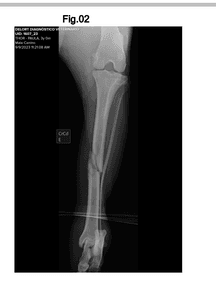

Oi aumigos, eu sou o Thor, moro aqui na rua do bairro. Me machuquei e preciso de uma cirurgia ortopédica. Meus vizinhos estão tentando me ajudar, fazendo essa vaquinha para a cirurgia.Sou um pouco levado, mas sou bonzinho e gosto muito daqui.

Meus vizinhos não sabe como me machuquei, sou um cachorro de rua, mas eles cuidam de mim.

O valor arrecadado, será exclusivamente para os cuidados do Thor, cirurgia e tratamento.